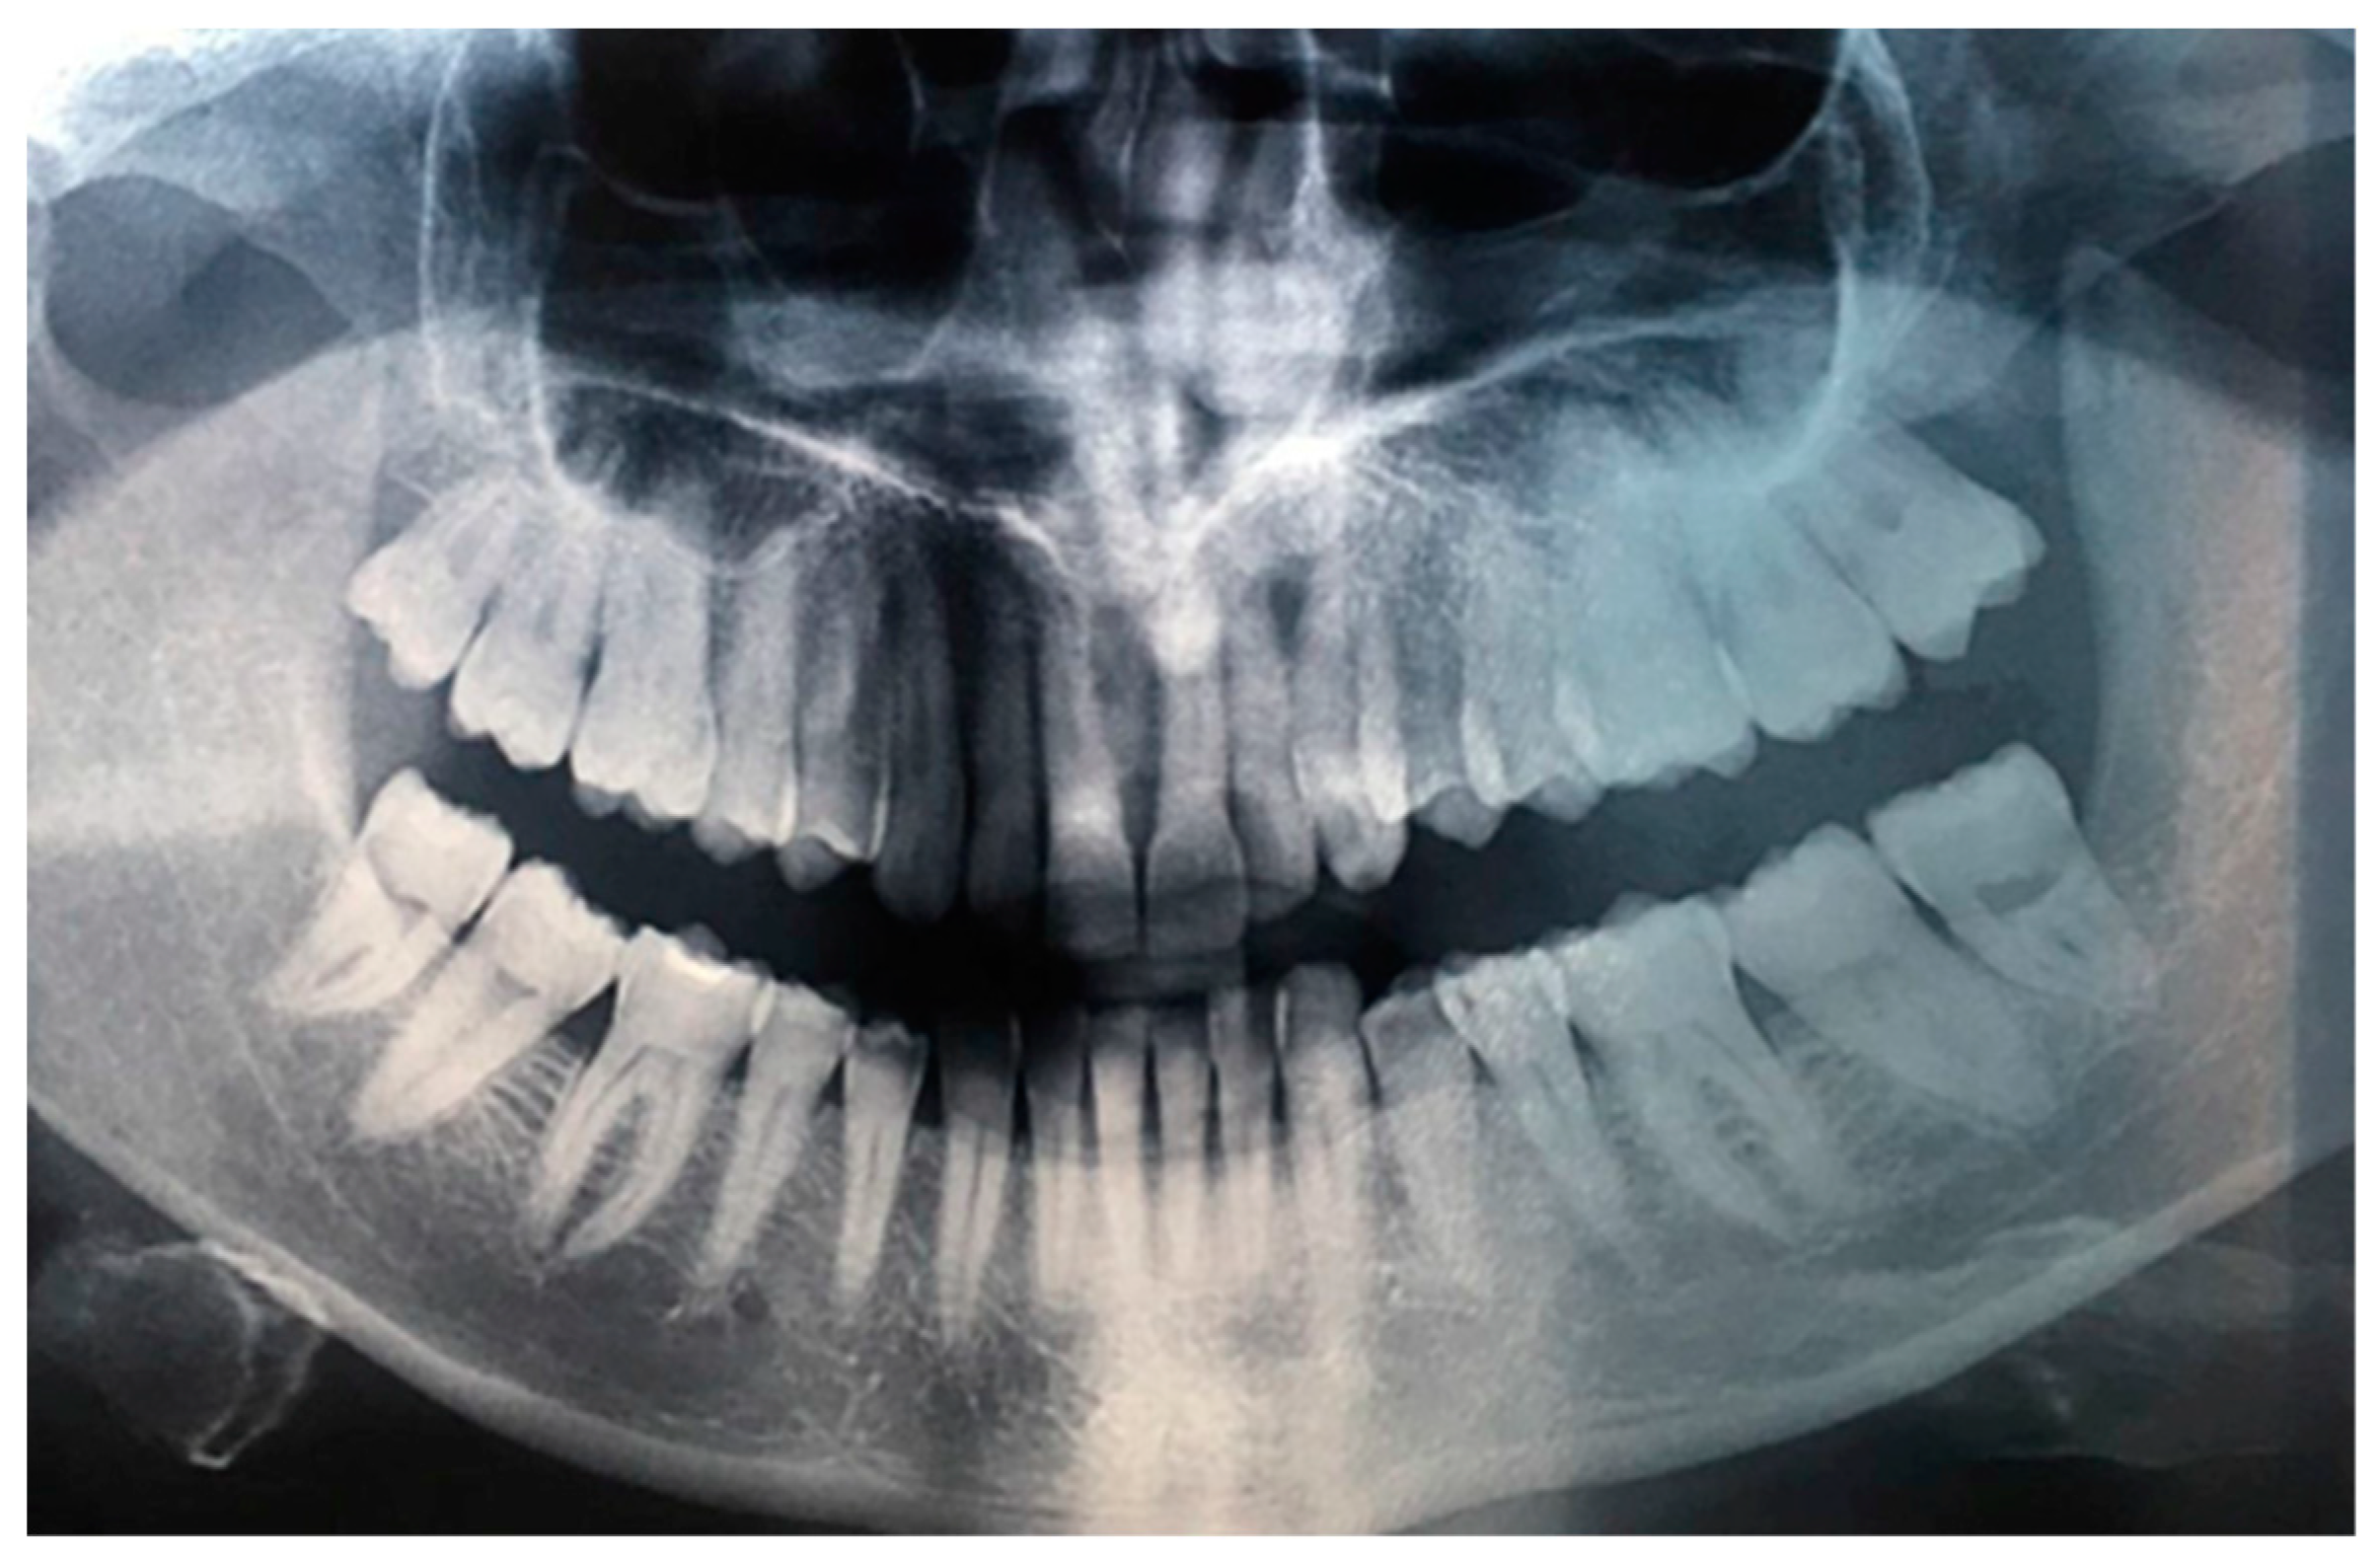

A 39-year-old Caucasian woman was referred to the Department of Oral and Maxillofacial Sciences of Polyclinic Umberto I, “Sapienza” University of Rome, for the presence of an exophytic and erythematous lesion located at the left retromolar trigonum (Figure 1), occurring since about 2 months, associated with a radiolucency evidenced by orthopanoramics (Figure 2).

Figure 1. Erythematous and exophytic lesion located at the left retromolar trigonum.